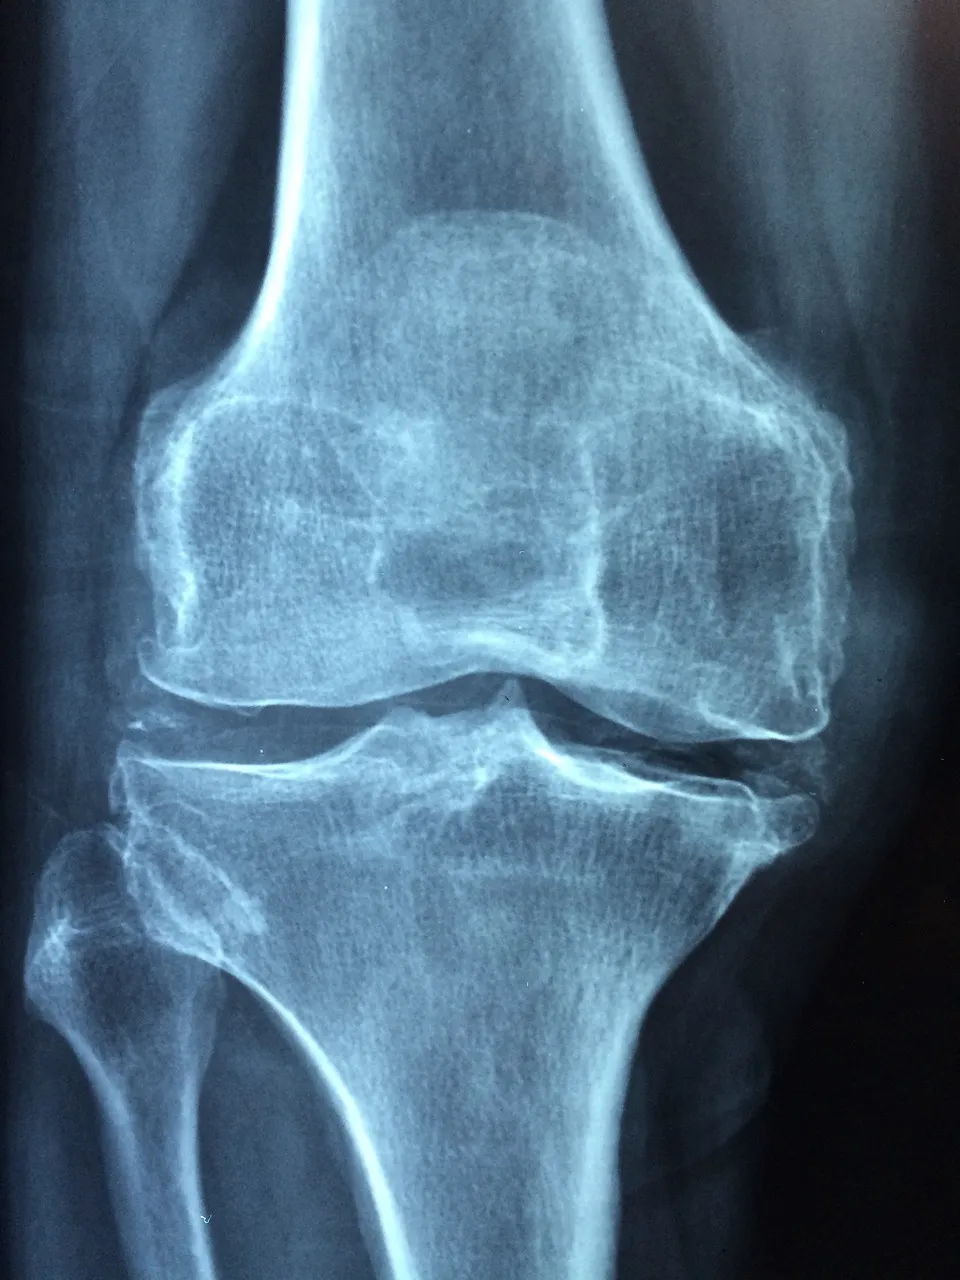

보스웰리아는 강력한 항산화 성분을 함유하고 있어, 염증을 일으키는 자유 라디칼을 제거합니다. 이로 인해 염증이 감소하고, 관절의 통증이나 부기가 완화되는 보스웰리아 효능이 있습니다.

보스웰리아는 소염 성분도 함유하고 있어, 염증을 줄이는 데 도움을 줍니다. 이러한 성분은 특히 류마티스 관절염이나 퇴행성 관절염 같은 질환에서 통증을 완화하는 데 효과적입니다.